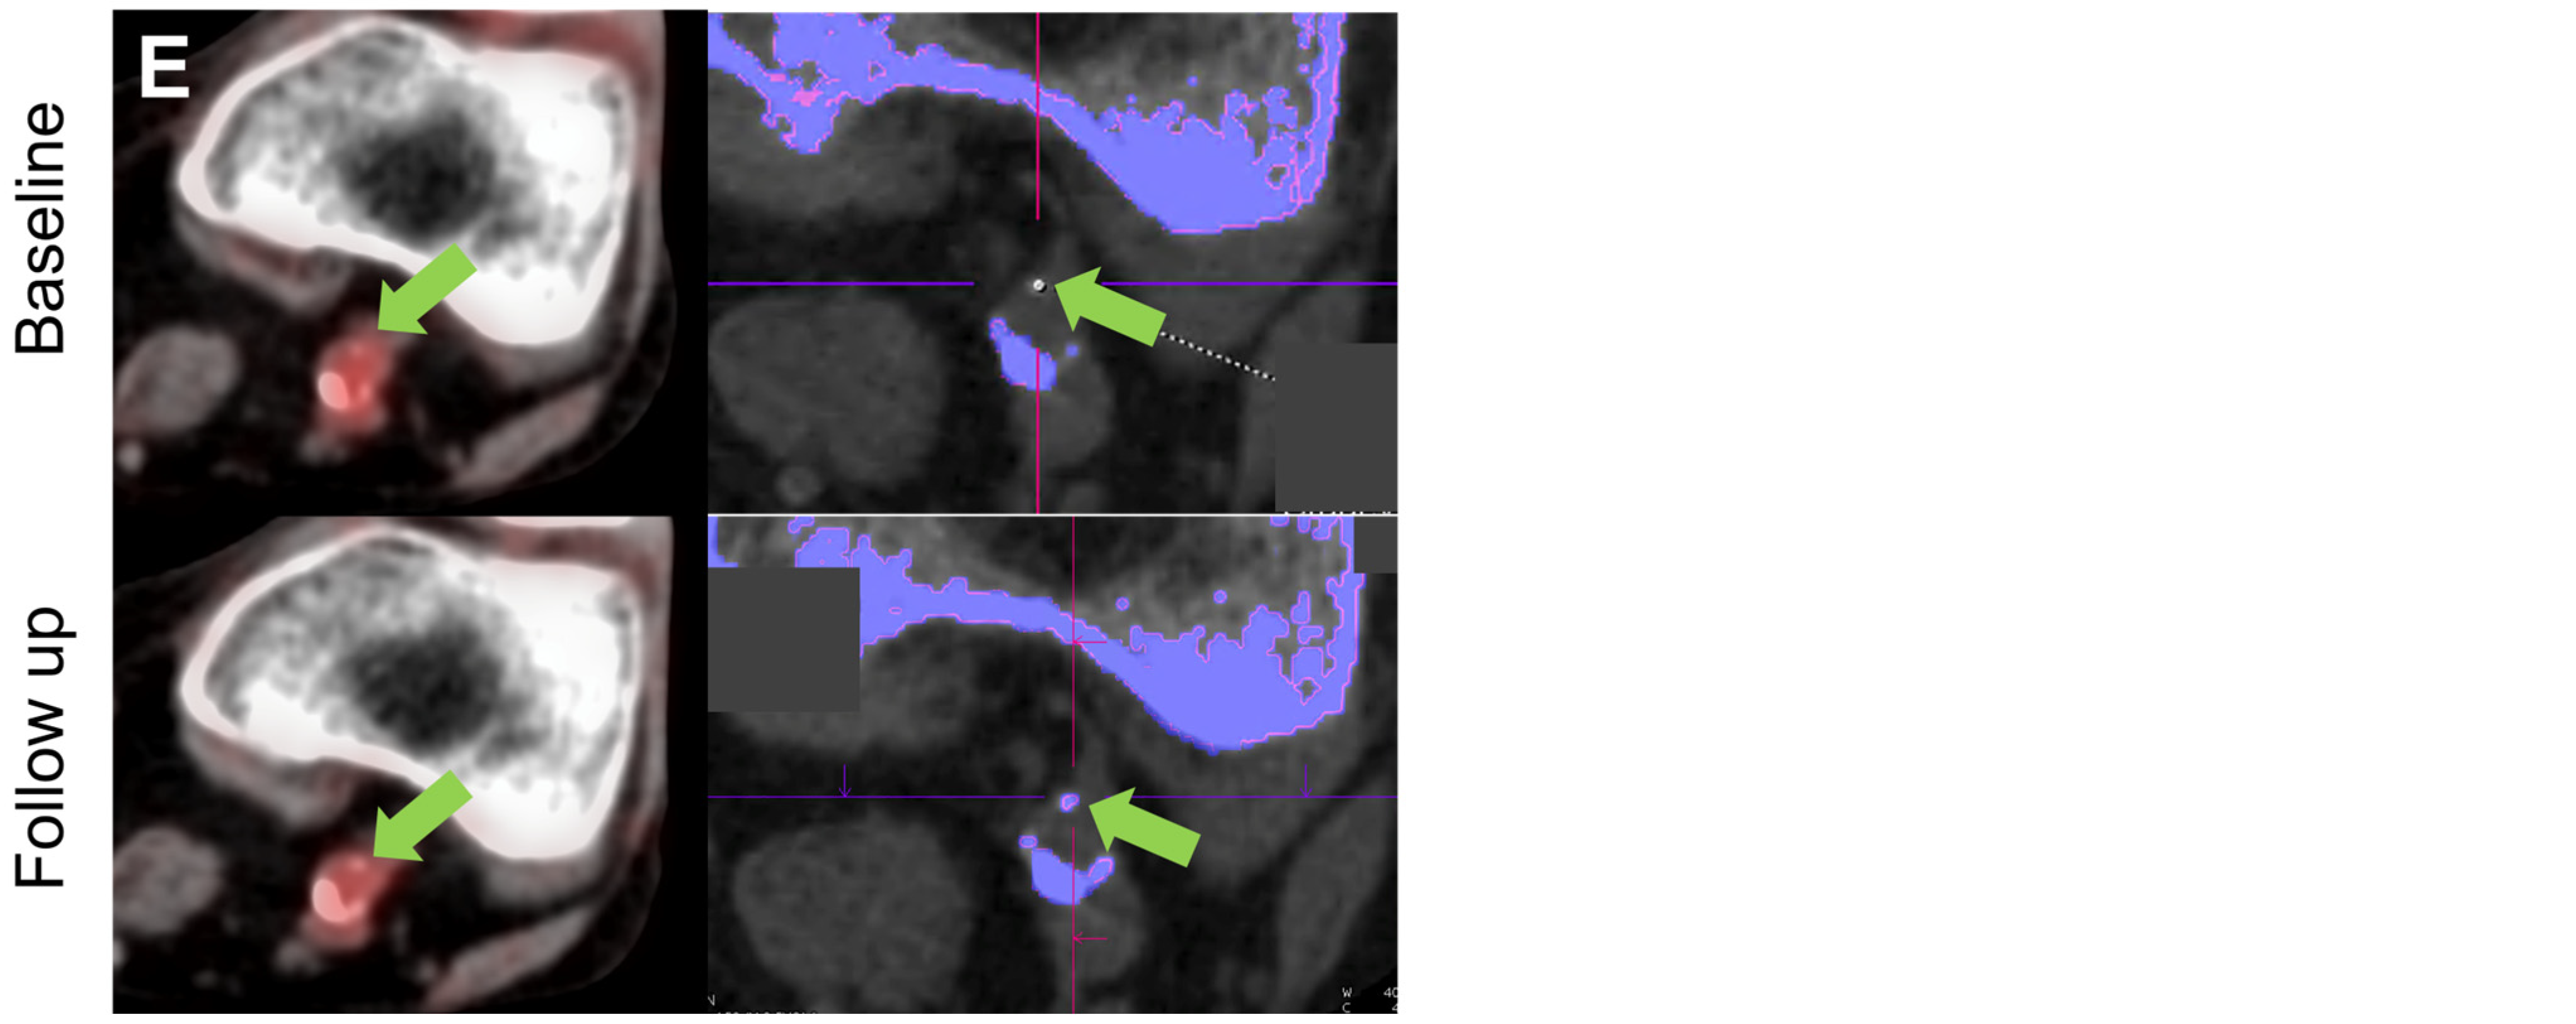

Representative 18F-FDG PET/CT and DECT images before and after Pegloticase treatment are shown in Figure 4. One patient demonstrated complete resolution of an MSU-coded deposit located in their abdominal aorta following Pegloticase treatment.

Figure 4.

Representative PET/CT (left) and DECT images (right) from axial locations in five vessel levels in four patients. (A) 18F-FDG uptake (orange overlay) shows inflammation in the right iliac artery (green arrow). On DECT, MSU-coded deposits (green) are shown in the corresponding vessel walls (green arrow), with bone (calcium) shown in purple. In this location, imaging shows a decrease in 18F-FDG uptake and MSU volume from baseline to follow-up following treatment with Pegloticase. (B) 18F-FDG uptake showing inflammation and DECT showing an MSU-coded deposit in the abdominal aorta (green arrows). In this patient, the deposit which was identified as MSU-coded at baseline, which likely had mixed calcium and MSU characteristics, appeared to resolve after treatment. 18F-FDG uptake in a small segment (~2 cm) of vessel centered on the location of the MSU-coded deposit showed a reduction in SUVmean from 1.81 to 1.68 and in SUVmax from 2.60 to 2.55. (C) 18F-FDG uptake in the abdominal aorta (green arrow) is reduced at follow-up (SUVmean/SUVmax pre: 1.65/2.17, post: 1.57/2.00) while MSU-coded deposit resolves. (D) In the descending thoracic aorta, little change is seen in 18F-FDG signal (SUVmean/SUVmax pre: 1.69/2.24, post: 1.64/2.26) while MSU-coded deposit volume increases from 1.3 mm3 to 3.4 mm3. (E) In the left femoral artery another MSU deposit resolves after treatment while 18F-FDG signal reduces slightly (SUVmean/SUVmax pre: 1.64/2.30, post: 1.64/2.25).